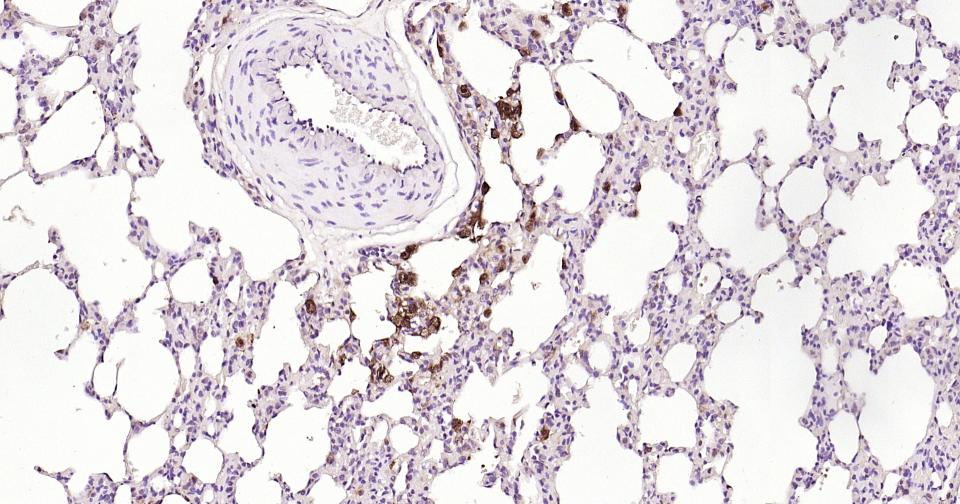

| IHC-P | Human, Mouse, Rat | 1:100-500 | |